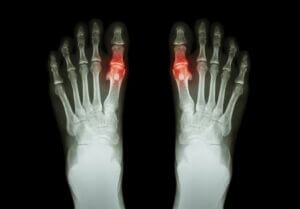

Fodsmerter har mange årsager, så lad os udforske nogle af dem her:

- Overvægt

- Flade fødder

- Deformiteter, såsom hammertæer

- Vorter

- Gigt

- Knoglesporer

- Plantar fasciitis

- Nedgroede tånegle osv.